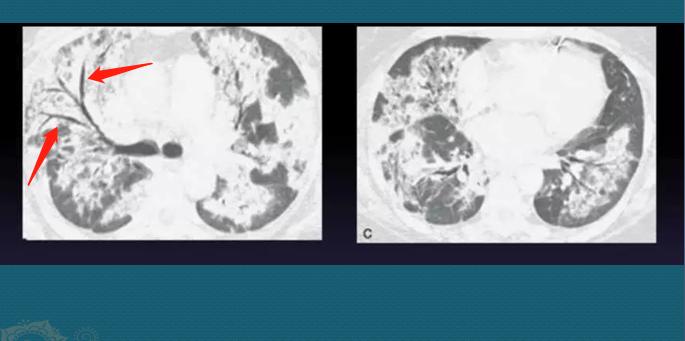

慢性病程者反复发作,继发肺泡间隔的慢性炎症,也可以出现肺纤维化表现,包括蜂窝状影、牵拉性支气管扩张、网格影等,提示预后差,尤其是出现蜂窝状改变。如下图:

肺间质纤维化形成“白肺”,支气管扩张

这位病人也是类似“白肺”的表现,是慢性肺泡出血、继发间质纤维化、支气管牵拉扩张所形成,跟新冠肺炎白肺的机制和发作速度都有不同。